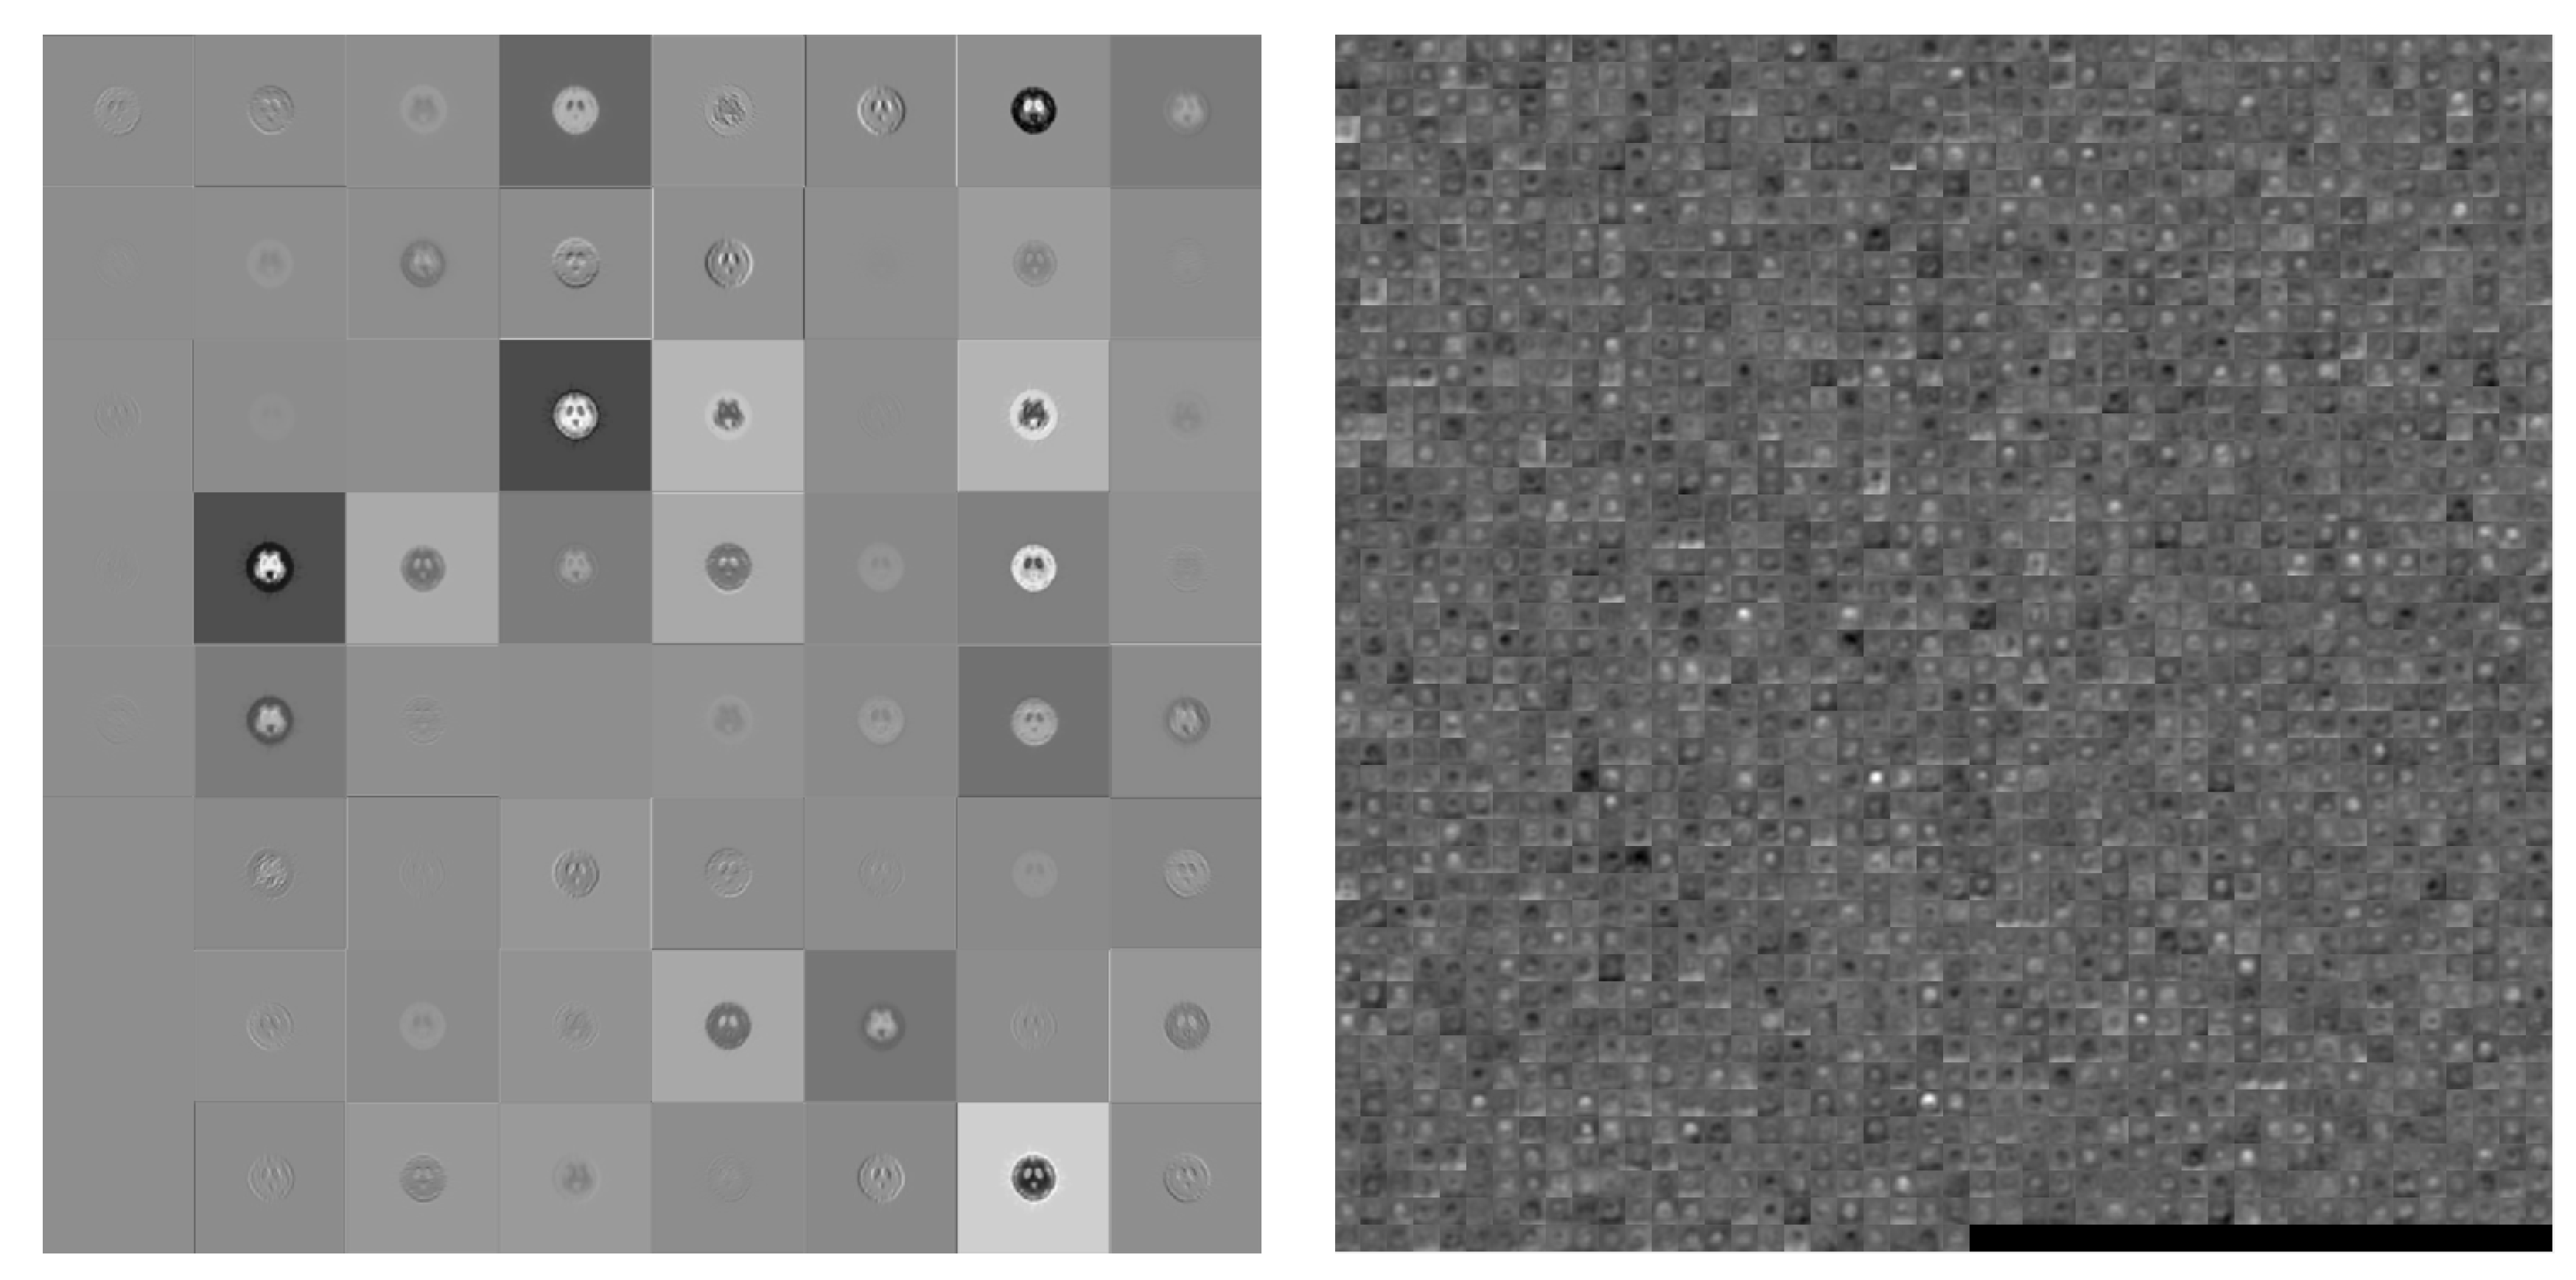

2.4.3. ResNet

| ResNet50 | 224 × 224 | 114 | 96 MB | 138.4 |

| ResNet101 | 224 × 224 | 347 | 167 MB | 326.1 |